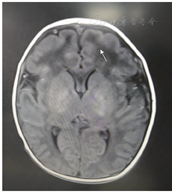

患儿男,生后4 d余,因"吸吮力弱、吃奶差3 d伴皮肤黄染1 d"入院。患儿系第2胎第2产,胎龄41周顺产娩出,无窒息史,出生体重3 900 g。生后吸吮力弱,吃奶少,第3天出现皮肤黄染,遂收入院。父母非近亲结婚,无特殊疾病家族史。入院查体:生命体征平稳,体重3 610 g,头围34.5 cm,身长52 cm,哭声低,皮肤中度黄染,心肺腹查体无异常。四肢肌张力低,原始反射减弱。入院时血清总胆红素262.5 μmol/L。入院2 h患儿出现呼吸减慢,经皮血氧饱和度低于0.90,予以鼻导管吸氧。血常规、C反应蛋白正常,血氨、血乳酸正常,TORCH-IgM阴性,甲状腺功能正常,胸部X线片、头颅B超、心脏B超正常,脑脊液及血尿串联质谱检测正常。头颅磁共振成像回报T1像发现额部稍低信号影(图1)。入院后行遗传病全外显子组家系检测,结果回报:父母基因检测均无异常,患儿为PURA(NM-005859.4)Exon1:c.98dupG;p. (Gly34fs)移码突变,提示5号染色体长臂3区1带PURA基因发生了移码突变,诊断PURA综合征。住院期间患儿吸吮力进行性减弱,需管饲喂养,呼吸浅慢、不能离氧,少哭少动,四肢肌张力尤其双下肢肌张力明显低下,家长考虑预后差,自动出院。出院后电话随访,曾在外院行高压氧治疗,但效果不明显,于生后1个半月余死亡。

PURA蛋白指富含嘌呤的元素结合蛋白A,由PURA基因编码,从细菌到人类高度保守。该蛋白具有多种作用,包括控制基因的活性并帮助修复DNA,参与神经细胞的生长和分裂、髓鞘的形成及成熟,促进神经冲动的有效传递,对正常的大脑发育尤为重要[1]。PURA综合征即PURA基因变异导致的一系列临床症状。PURA基因位于5q31区带q31.3位点,5q31.3微缺失可导致PURA综合征相关症状[2]。本病新生儿期主要表现为喂养困难,肌张力低下,呼吸功能不全,随后出现精神运动发育严重迟缓等。本病罕见,目前国内未曾报道。全球大约有70例PURA综合征报道。Reijnders等[3]对32例PURA综合征(含22例先前报道发病的病例)进行分析,显示新生儿期症状包括肌张力减退(96%)、喂养困难(77%)、过度嗜睡(66%)、呼吸系统疾病(57%)、夸大的惊恐反应( 44%)和体温过低(35%),该研究对32例患儿面部照片进行计算分析,显示微妙的面部畸形,认为新生儿期"肌病面容"可能有助于临床诊断,但未发现基因型-表型之间的强相关性。本例患儿无明显异常面部特征。英国Hunt等[4]对1 000多例不明原因的智力障碍患儿进行全外显子测序,发现4例PURA基因突变,导致严重的神经发育迟缓和学习障碍,患儿新生儿期肌张力减低和喂养困难,其中1例出生1周时头颅磁共振成像出现不均匀斑片状衰减信号影,额部尤为明显。本例患儿头颅磁共振成像亦在额部有信号减低影。如临床发现新生儿生后无诱因出现肌张力减低、喂养困难、呼吸功能不全,除与Prader-Willi综合征、先天性脊肌萎缩症、肌营养不良等相鉴别外,可考虑PURA综合征,尽早行遗传学全外显子检测以明确诊断。